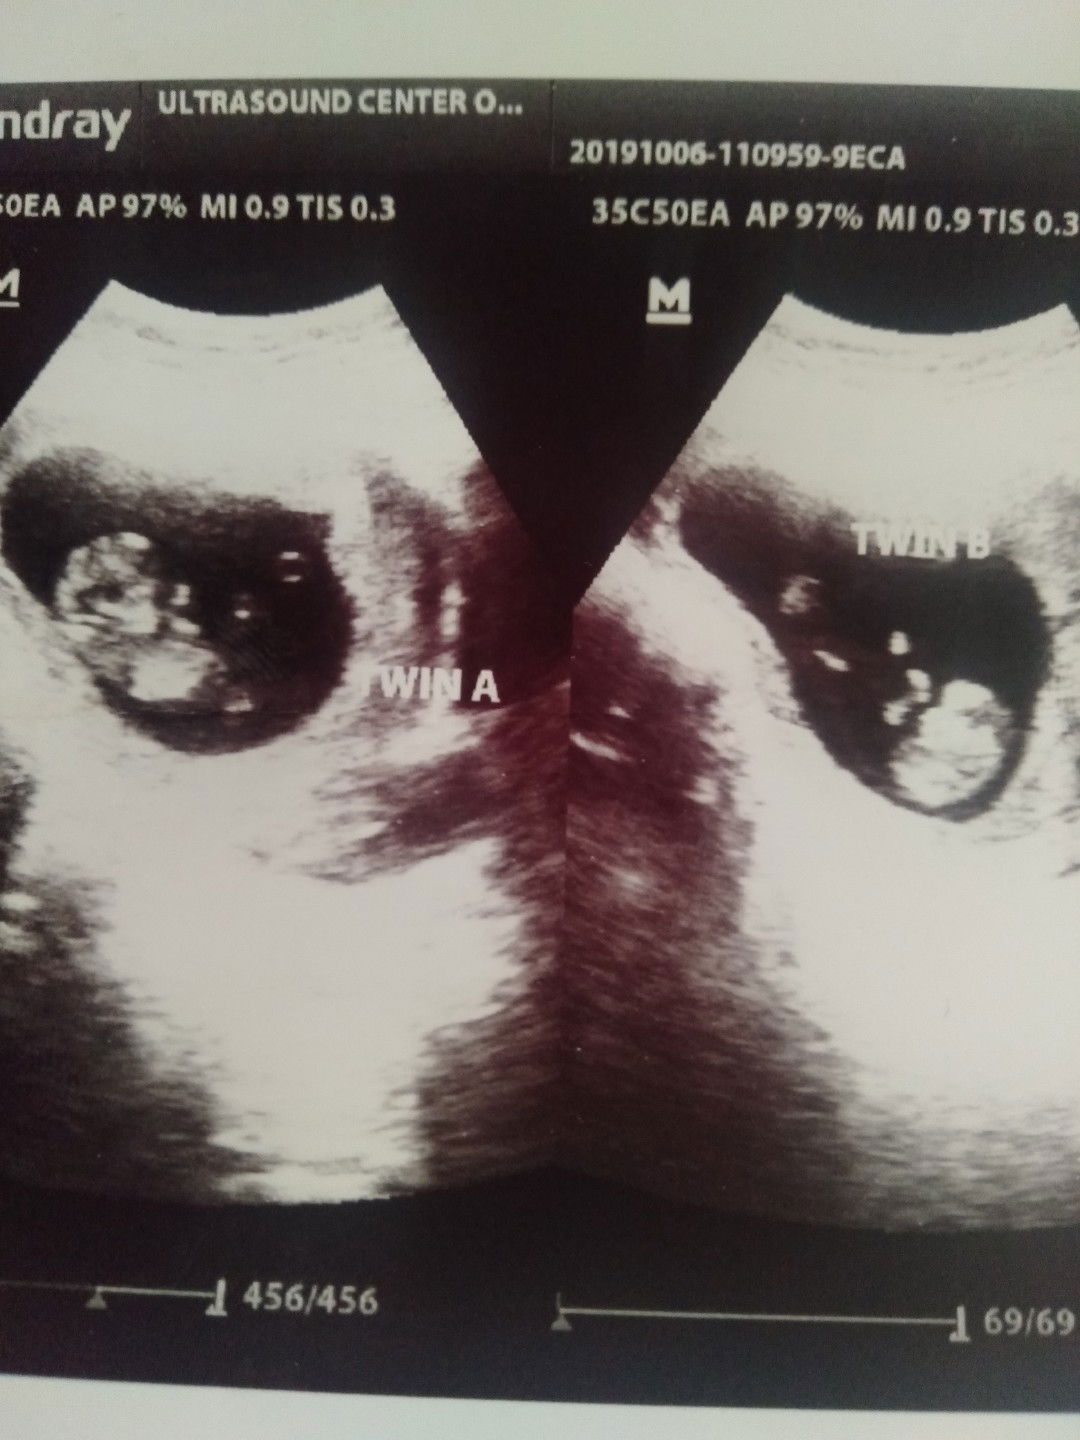

ano po magandang name para sa baby ko pong twin qng baby boy cla or baby girl oh di kaya boy'girl ng twin..? initial letter R and J

Ndi pa malaman gender nila kc 11 weeks and 3 days plang CLA Jan..????